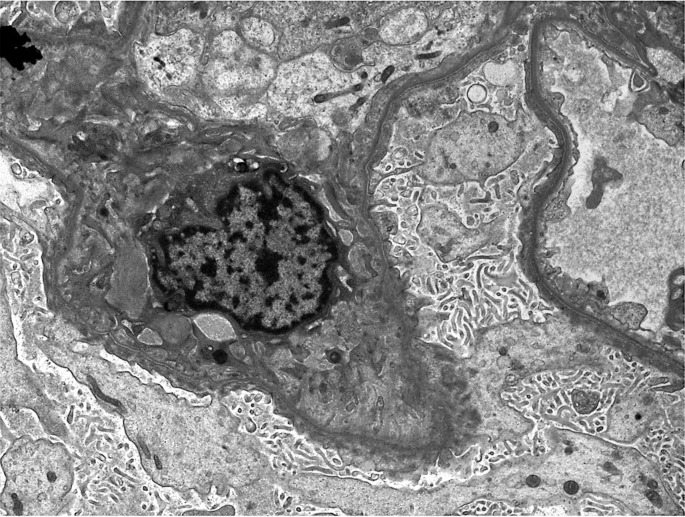

Presentation: Here we present a case of biopsy-proven minimal change disease in a patient with PBC treated with a course of steroids and achieving complete recovery.